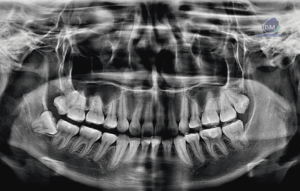

Paciente femenino de 39 años de edad, es referido al Instituto de Diagnóstico Maxilofacial – IDM para evaluación general.En la radiografía panorámica (Figura 1), se